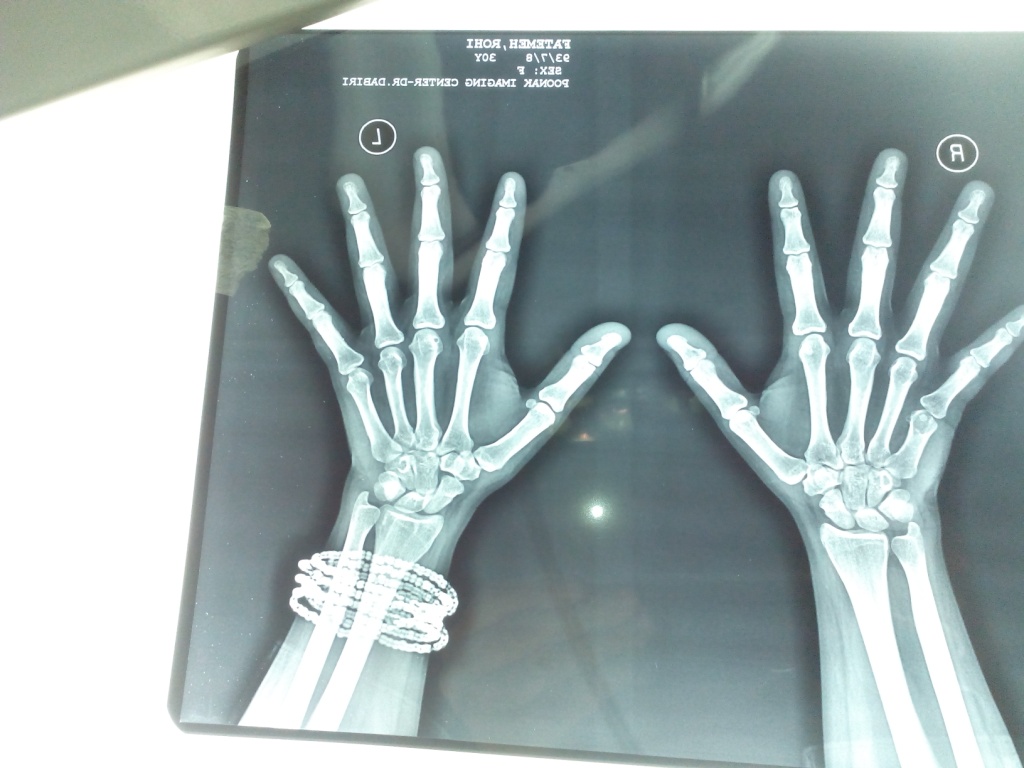

ده روز بعد عمل

جدید ترین عکس تاریخ 93/8/1